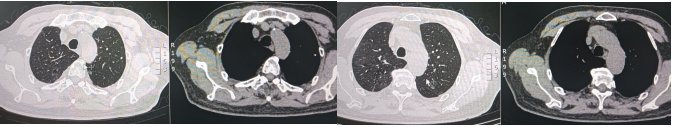

入院后给予奈诺沙星0.5 g qd ivgtt、头孢他啶阿维巴坦2.5 g q8h ivgtt经验性抗感染治疗。治疗5天后复查相关指标:白细胞计数9.69×109/L,中性粒细胞绝对数7.31×109/L,C反应蛋白90.4 mg/ml,血清淀粉样蛋白>288.00 mg/L,红细胞沉降率测定94 mm/h;胸部CT:右肺上叶、下叶间质性炎症,左下肺小结节,炎性结节可能(图2)。提示病变无明显好转,告知家属病情后再次行气管镜检查,行病原学检查及病理检查,结果示:BALF涂片、培养、GM均阴性;BALF NGS回报:流感嗜血杆菌、烟曲霉。冷冻肺活检病理:(右肺下叶后基底段)肺组织急、慢性炎,肺泡腔内见纤维素样渗出物伴泡沫细胞聚集。免疫组化结果:CK7(+),TTF1(+),SMA(平滑肌+),NapsinA(+),PGM-1(+),Ki-67(+, 5%),P40(+),CD68(+)。考虑真菌感染不除外于8月31日加用伏立康唑0.2 g q12h ivgtt;醋酸卡泊芬净70 mg qd ivgtt抗真菌对症治疗。图2 2024年8月27日复查胸部CT较8月21日胸部CT无明显吸收9月5日再次复查相关指标:白细胞计数12.38×109/L,中性粒细胞绝对数9.27×109/L,C反应蛋白151.46 mg/ml,血清淀粉样蛋白>288.00 mg/L,红细胞沉降率117 mm/h。胸部CT:右肺散在间质性炎症,左下肺新发炎症灶,较前进展,左下肺小结节,范围较前增大(图3)。图3 2024年9月5日胸部CT右下肺炎症较8月27日进展,左肺出现新发炎症灶9月5日行MDT讨论,考虑感染继发机化性肺炎不除外,建议在目前抗感染治疗保驾下予中等剂量激素治疗,并严密动态观察相关指标。9月6日起治疗上加用甲泼尼龙琥珀酸钠80 mg qd ivgtt。治疗1周后(9月12日)复查相关指标:复查炎症标志物:白细胞计数16.47×109/L,中性粒细胞绝对数14.79×109/L,C反应蛋白11.08 mg/ml,血清淀粉样蛋白25.388 mg/L,红细胞沉降率28 mm/h。胸部CT:双肺散在间质性炎症(右肺为著),较前吸收(图4)。9月12日调整激素剂量为醋酸泼尼松片35 mg qd口服;9月19日患者无发热,无明显咳嗽、咳痰不适,予出院并嘱出院后维持醋酸泼尼松片35 mg qd口服,1周后每周减5 mg,减至20 mg后维持1周并复查胸部CT,根据胸部CT结果调整剂量。10月21日患者门诊复查胸部(图5),较前明显吸收,激素调整为醋酸泼尼松片10 mg qd,目前在持续随访中。治疗期间感染相关指标变化情况如图6所示。机化性肺炎(organizing pneumonia,OP)是一种肺组织修复过程,是以肺泡腔/管内有息肉状肉芽组织为病理特点,主要由成纤维细胞、肌成纤维细胞和疏松结缔组织基质构成[1]。同时与其他肺损害,如血管炎、淋巴瘤、肺癌、过敏性肺炎(hypersensitivity pneumonitis,HP)、嗜酸性粒细胞性肺炎(eosinophilic pneumonia,EP)、急性间质性肺炎(acute interstitial pneumonia,AIP)、非特异性间质性肺炎(nonspecific interstitial pneumonia,NSIP)或普通型间质性肺炎(usual interstitial pneumonia,UIP)关系密切。OP具有复杂的多态性,具有急性、亚急性和慢性多种形式。OP可以根据病因分为隐源性机化性肺炎(cryptogenic organizing pneumonia,COP)和继发性机化性肺炎(secondary organizing pneumonia,SOP)。COP与SOP在临床表现、影像表现和肺功能无明显差异[2],当有相关病因时诊断为SOP,当临床未发现相关潜在疾病时诊断为COP。OP的概念最早在肺炎链球菌的大叶性肺炎中被阐述,OP的发病机制目前主要认为肺泡上皮损伤,纤维蛋白渗出,导致成纤维细胞增生-肌成纤维细胞增生[3]。机化存在于多种肺损伤中,具有相同的本质,无论是局灶性还是弥漫性肺损伤,以成纤维细胞增殖为特征的机化是一种常见且几乎普遍的反应[4],机化被认为是对炎症渗出的反应和局限,很可能代表疾病的一个阶段,而不是独立的疾病。所以如果有确认感染的证据,虽然CT上发现有机化的特征,临床诊断OP往往是不必要的,除非这种机化是主要表现,而且改变了疾病进程。因此关注整体,将OP作为疾病的一个阶段,有利于建立对疾病的全息认识。OP没有特异的临床特征,患者可能出现发热、咳嗽、乏力、轻度呼吸困难、厌食症和体重减轻等,类似于流感[5],临床表现不特异。有些患者接受经验性抗生素治疗后往往无效,且疾病可能会迅速进展,导致严重的呼吸困难,甚至是ARDS,往往存在延误诊断。有文献报道大部分OP患者为不吸烟患者,肺功能主要表现为限制性通气障碍,也可表现为混合型和阻塞性通气障碍[6]。也有学者研究SOP患者有胸腔积液,而COP患者未报告胸腔积液[7]。因此,胸腔积液似乎与背景疾病有关,而与OP本身无关。OP的CT表现可以按照发生率分为典型和非典型模式[6],多数患者表现为典型模式,即多灶性实变,常被描述为斑片状肺泡阴影,一般位于下肺外周或支气管血管周围;实变可伴有支气管充气征,并可伴有散在的磨玻璃病变或小结节。而非典型的病变表现多样,可为磨玻璃影,也可为结节或肿块样表现、反晕征、铺路石征、小叶周围病变、线性和带状阴影以及网状结构。OP虽然有多种影像学表现,但均不特异,类似的表现同样可以出现在其他疾病中。例如,迁移性病灶可提示嗜酸性粒细胞性肺炎、感染、血管炎和复发性出血[8];弥漫性微小结节可见于过敏性肺炎、细支气管感染和炎症;反晕征可见于多种感染、非感染性肉芽肿异常,甚至原位腺癌[9]。因此诊断OP不能单纯依靠CT,需要结合临床和病理特征。目前针对OP的治疗,COP主要是以糖皮质激素为主[10],SOP需要兼顾原发疾病治疗及激素应用,因此我们需要尽早明确病理,及时治疗,减少不良预后。针对重症患者,尽早获取病理是必要的。此病例我们初步诊断为CAP,予抗感染治疗后疾病进展,及时行二次支气管镜冷冻肺活检+灌洗,同时通过mNGS及病理检查,最终被诊断为SOP,经激素抗炎治疗后症状好转,影像学提示病灶明显吸收。总之,OP在临床上并不少见,但由于其临床表现无特异性且CT表现多样,所以及时正确诊断OP罕见,诊断OP需要结合临床和病理特征,只有当OP成为主导性特征且干扰了疾病进程,才被冠以OP的诊断。针对初诊为肺炎的患者,当经验性抗感染治疗效果欠佳时,需要及时明确病原学检查及病理诊断,及时修改诊断及治疗路径,及时干预[11]。[1] CottinV,CordierJF. Cryptogenic organizing pneumonia[J]. Semin Respir Crit Care Med, 2012, 33(5): 462-475.